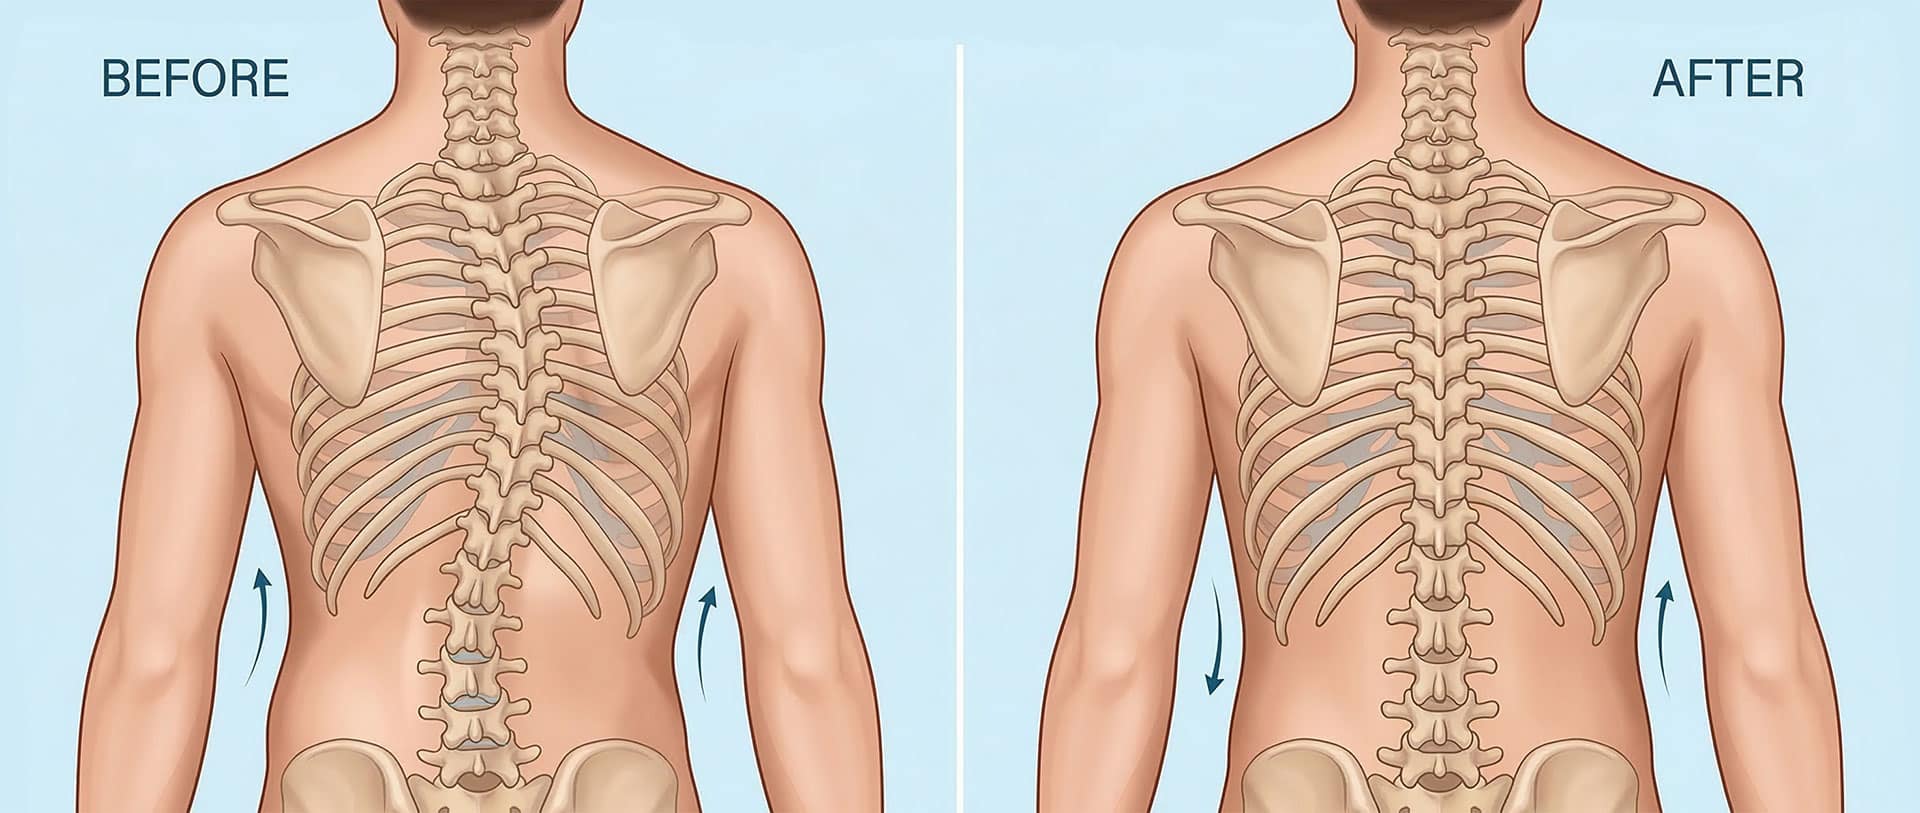

Scoliosis is measured on x-ray as a Cobb Angle. This measurement tells us how bad the scoliosis is and then guides us in how we treat it. Curves under 10 degrees usually aren’t considered scoliosis. Those curves 10-25 are called mild curves and we treat them with scoliosis specific exercise. Curves 25-45 degrees are treated with scoliosis specific exercise and bracing. Those above 45 degrees are usually surgical candidates. There is a measurement error of 3-5 degrees, which means to really have significant change, it needs to be above that.

Here are some examples of what can be done with scoliosis specific exercise with a variety of patients. The main goal of treatment is to STOP progression of the curve. With hard work and dedication we can also see reduction in the curve.